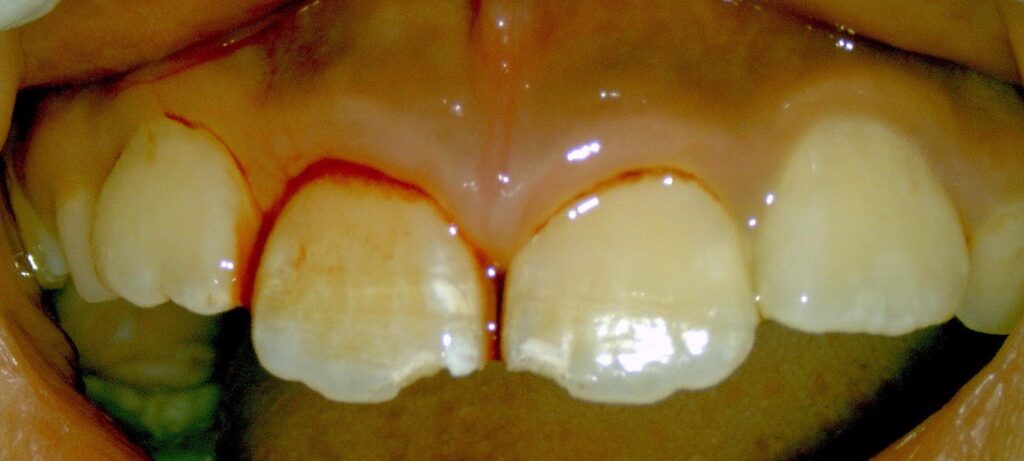

①ベットの上で飛び跳ねていてベッドの背に顔をぶつけた

②友達と遊んでいて友達の肘や頭が自分の前歯に当たった

③鉄棒中に手が滑って鉄棒に前歯をぶつけた

④バスケットやラグビーの練習中に相手の頭に前歯がぶつかった、など)

処置)歯の神経が残る場合があります。すぐにプラスチック(レジン充填)で揺れを止め経過観察をします。